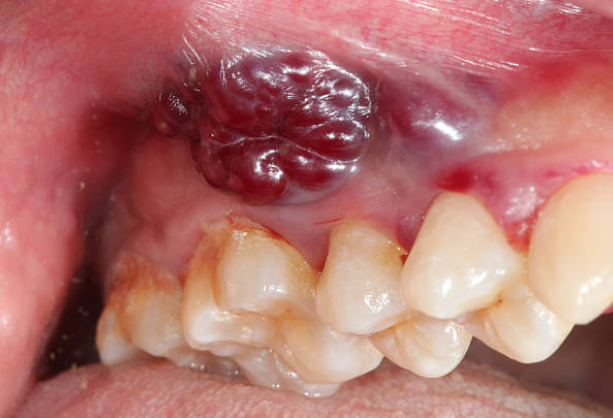

Oral cancer is a type of cancer that affects the mouth, throat, tongue, and lips. It is estimated that approximately 53,000 people in the United States will be diagnosed with oral cancer in 2023, and around 10,860 will die from the disease. This makes oral cancer one of the deadliest forms of cancer. In this article, we will explore why oral cancers kill and what can be done to prevent this deadly disease.

The primary reason why oral cancers kill is that they are often diagnosed late, which means that cancer has already spread to other parts of the body. Early detection is crucial when it comes to treating any form of cancer, especially so with oral cancer. Unfortunately, oral cancer is often not detected until it has reached an advanced stage, which makes it difficult to treat.

One of the reasons why oral cancer is difficult to detect early is because it can be asymptomatic, meaning that there are no obvious symptoms in the early stages of the disease. Some of the most common symptoms of oral cancer include a sore throat, difficulty swallowing, and pain or discomfort in the mouth or throat. However, these symptoms can be easily mistaken for other conditions, which can lead to a delayed diagnosis.

Another reason why oral cancer is difficult to detect early is that it can develop in hard-to-see areas of the mouth, such as the back of the throat or the base of the tongue. These areas are not always visible during a routine oral exam, which means that early signs of oral cancer may be missed.